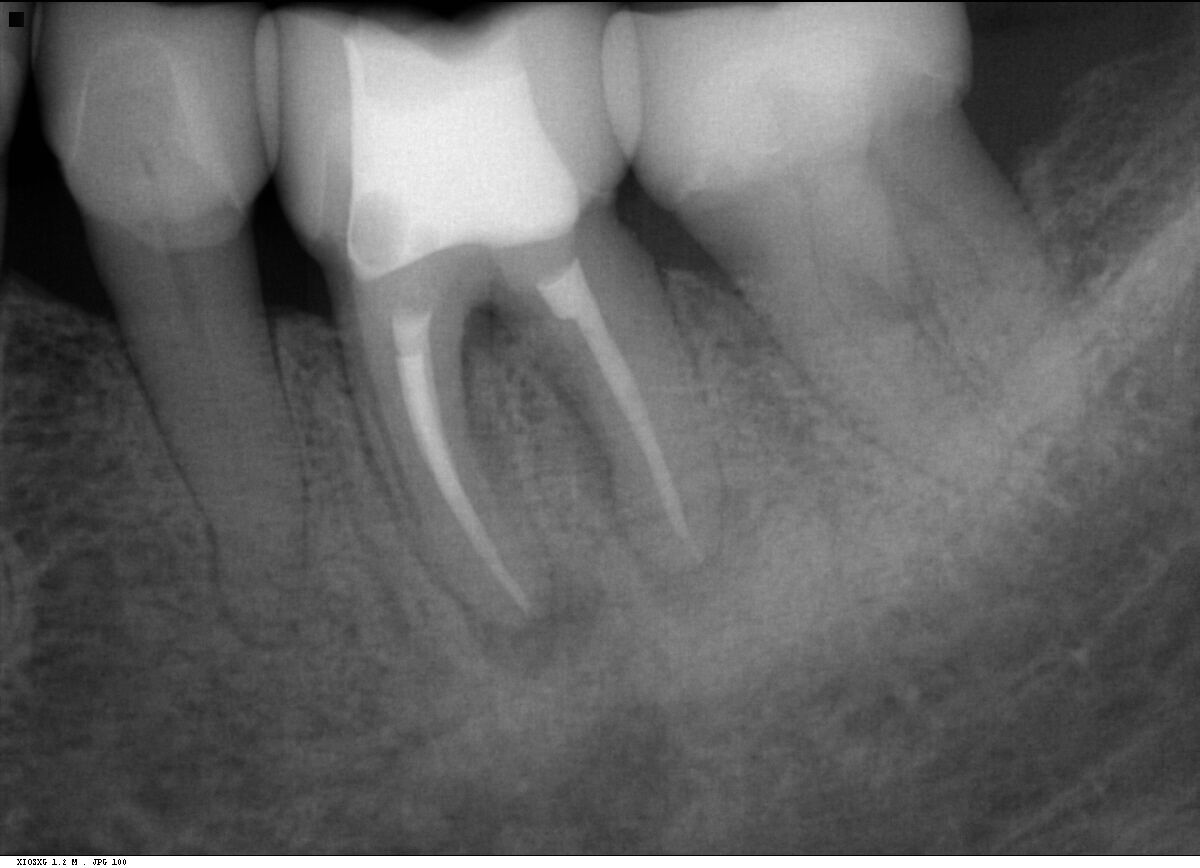

Fall 4: großer interradikulärer Entzündungsherd

Endodontie Fall 4: großer interradikulärer Entzündungsherd

Vor der Behandlung